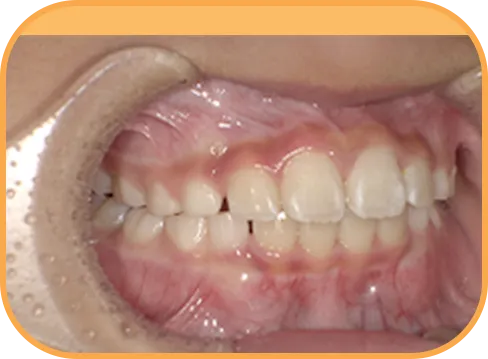

• 右 側

治療後右側からの歯の様子

• 左 側

治療後左側からの歯の様子

主 訴

前歯ガタガタ、前歯が大きい

治療内容

インビザライン・ファースト

治療期間

7か月

治療費(税別)

450,000円+診断料5,000円

リスク・副作用

• 親知らずの影響や加齢などによって、凸凹が生じる可能性があります。

• 治療の初期段階では痛みや不快感が生じやすくなりますが、1週間前後で慣れます。

• 顎の成長発育によって、噛み合わせや歯並びが変化する可能性があります。

• 状況により当初予定した治療計画を変更する可能性があります。